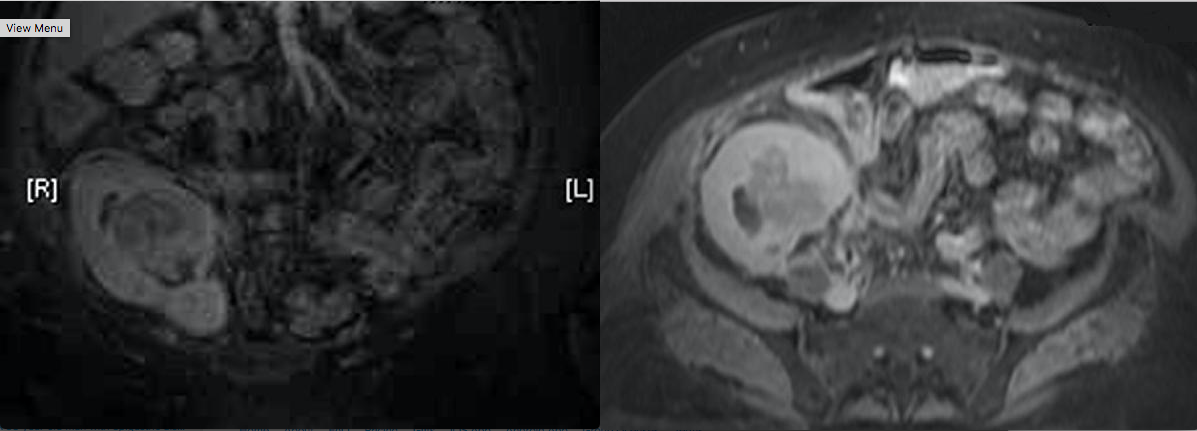

A 71-year-old woman develops a mass in the allograft two years after renal transplant. Needle biopsy of the mass reveals a large B cell lymphoma. Representative images from the MRI scan are shown in exhibits 1 and 2. The next step is:

1 reduce immunosuppression

Post transplant lymphomas are most commonly non-Hodgkin and associated with Epstein-Barr virus infection. The reported incidence ranges from 0.8 to 15, and varies with the type of immunosuppression utilized. These tumors may respond to drastic reduction or withdrawal of immunosuppression. Standard chemotherapy and irradiation are not generally effective and may exaggerate the degree of immune compromise. Treatment with anti-viral medications such as gancyclovir may be beneficial. Nephrectomy may be necessary, but is not the initial treatment.